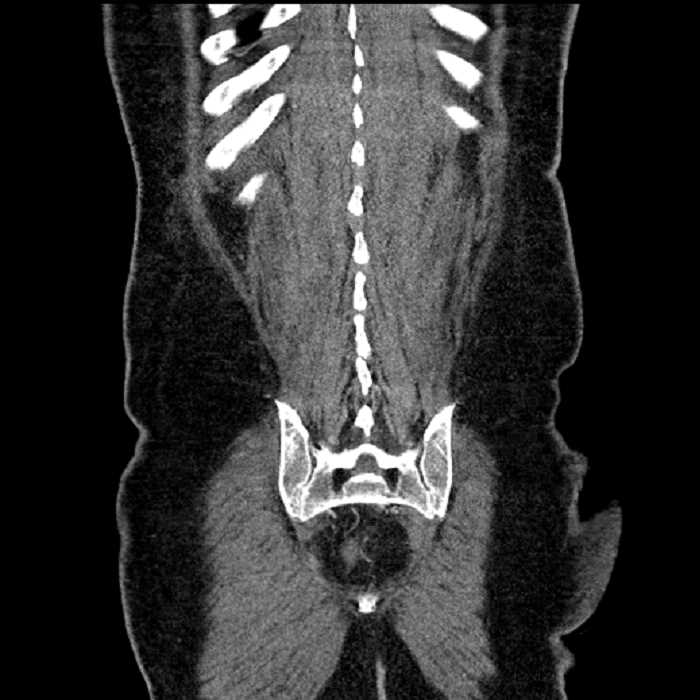

• High grade stenosis of the left common iliac artery, with the left internal and external iliac arteries remaining patent

• Ankylosis of both sacroiliac joints

• Circumscribed sclerotic lesion in the left anterolateral seventh rib without aggressive features, likely a bone island

High grade stenosis of the left common iliac artery. The left external and internal iliac arteries are patent.